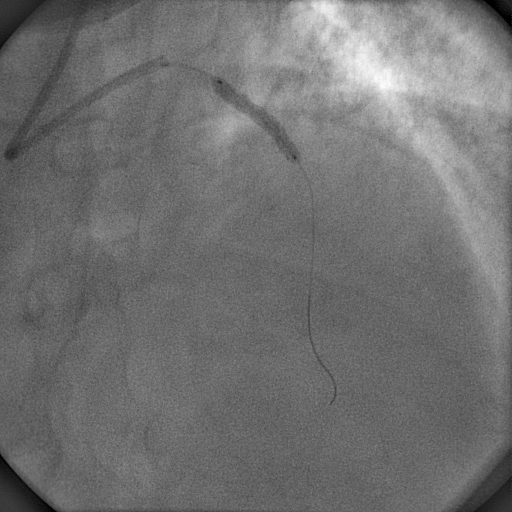

A 6 r XB guiding catheter was chosen to cannulate the left coronary artery. A PT2 hydrophilic guidewire was used to cross the totally occluded LAD lesion with a 2x10mm Sapphire balloon for support (Figure 3). The occluded segment was dilated using the same balloon at 18atm. A 3x25mm Cre 8 stent (DES, CID, Italy) was deployed in the ostioproximal LAD at 18atm (Figure 4) and post-dilated using a 3.5x10mm Sapphire NC at 20 atm (Figure 5). TIMI III flow was established (Figure 6). The patient was hemodynamically stable, and a minimum amount of contrast was used to prevent much volume overload. Then a 6Fr JR guiding catheter was selected in an attempt to engage the right coronary artery, but extreme coiling and kinking made it impossible to cannulate the RCA properly. So keeping the diagnostic guidewire in situ with the catheter tip far from RCA ostium, the PT2 guidewire was used to wire the RCA with a 2x10 mm balloon support (Figure 7, Figure 8). Keeping the balloon in the proximal RCA, the guiding catheter could be advanced over the balloon catheter to engage the right coronary artery properly. Using a buddy wire, the lesion was dilated with the same balloon at 14atml and a 2.75x23mm CC Flex (CoCr) stent was deployed at 18atm (Figure 9). Distal TIMI III flow as achieved (Figure 10).